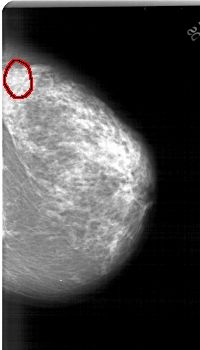

A_1315_1.RIGHT_CC

RIGHT_CC LINES 5941 PIXELS_PER_LINE 3391 BITS_PER_PIXEL 12 RESOLUTION 43.5 OVERLAY

FILE: A_1315_1.RIGHT_CC.OVERLAY

TOTAL_ABNORMALITIES 1

ABNORMALITY 1

LESION_TYPE CALCIFICATION TYPE PLEOMORPHIC DISTRIBUTION CLUSTERED

ASSESSMENT 4

SUBTLETY 2

PATHOLOGY BENIGN

TOTAL_OUTLINES 1

BOUNDARY